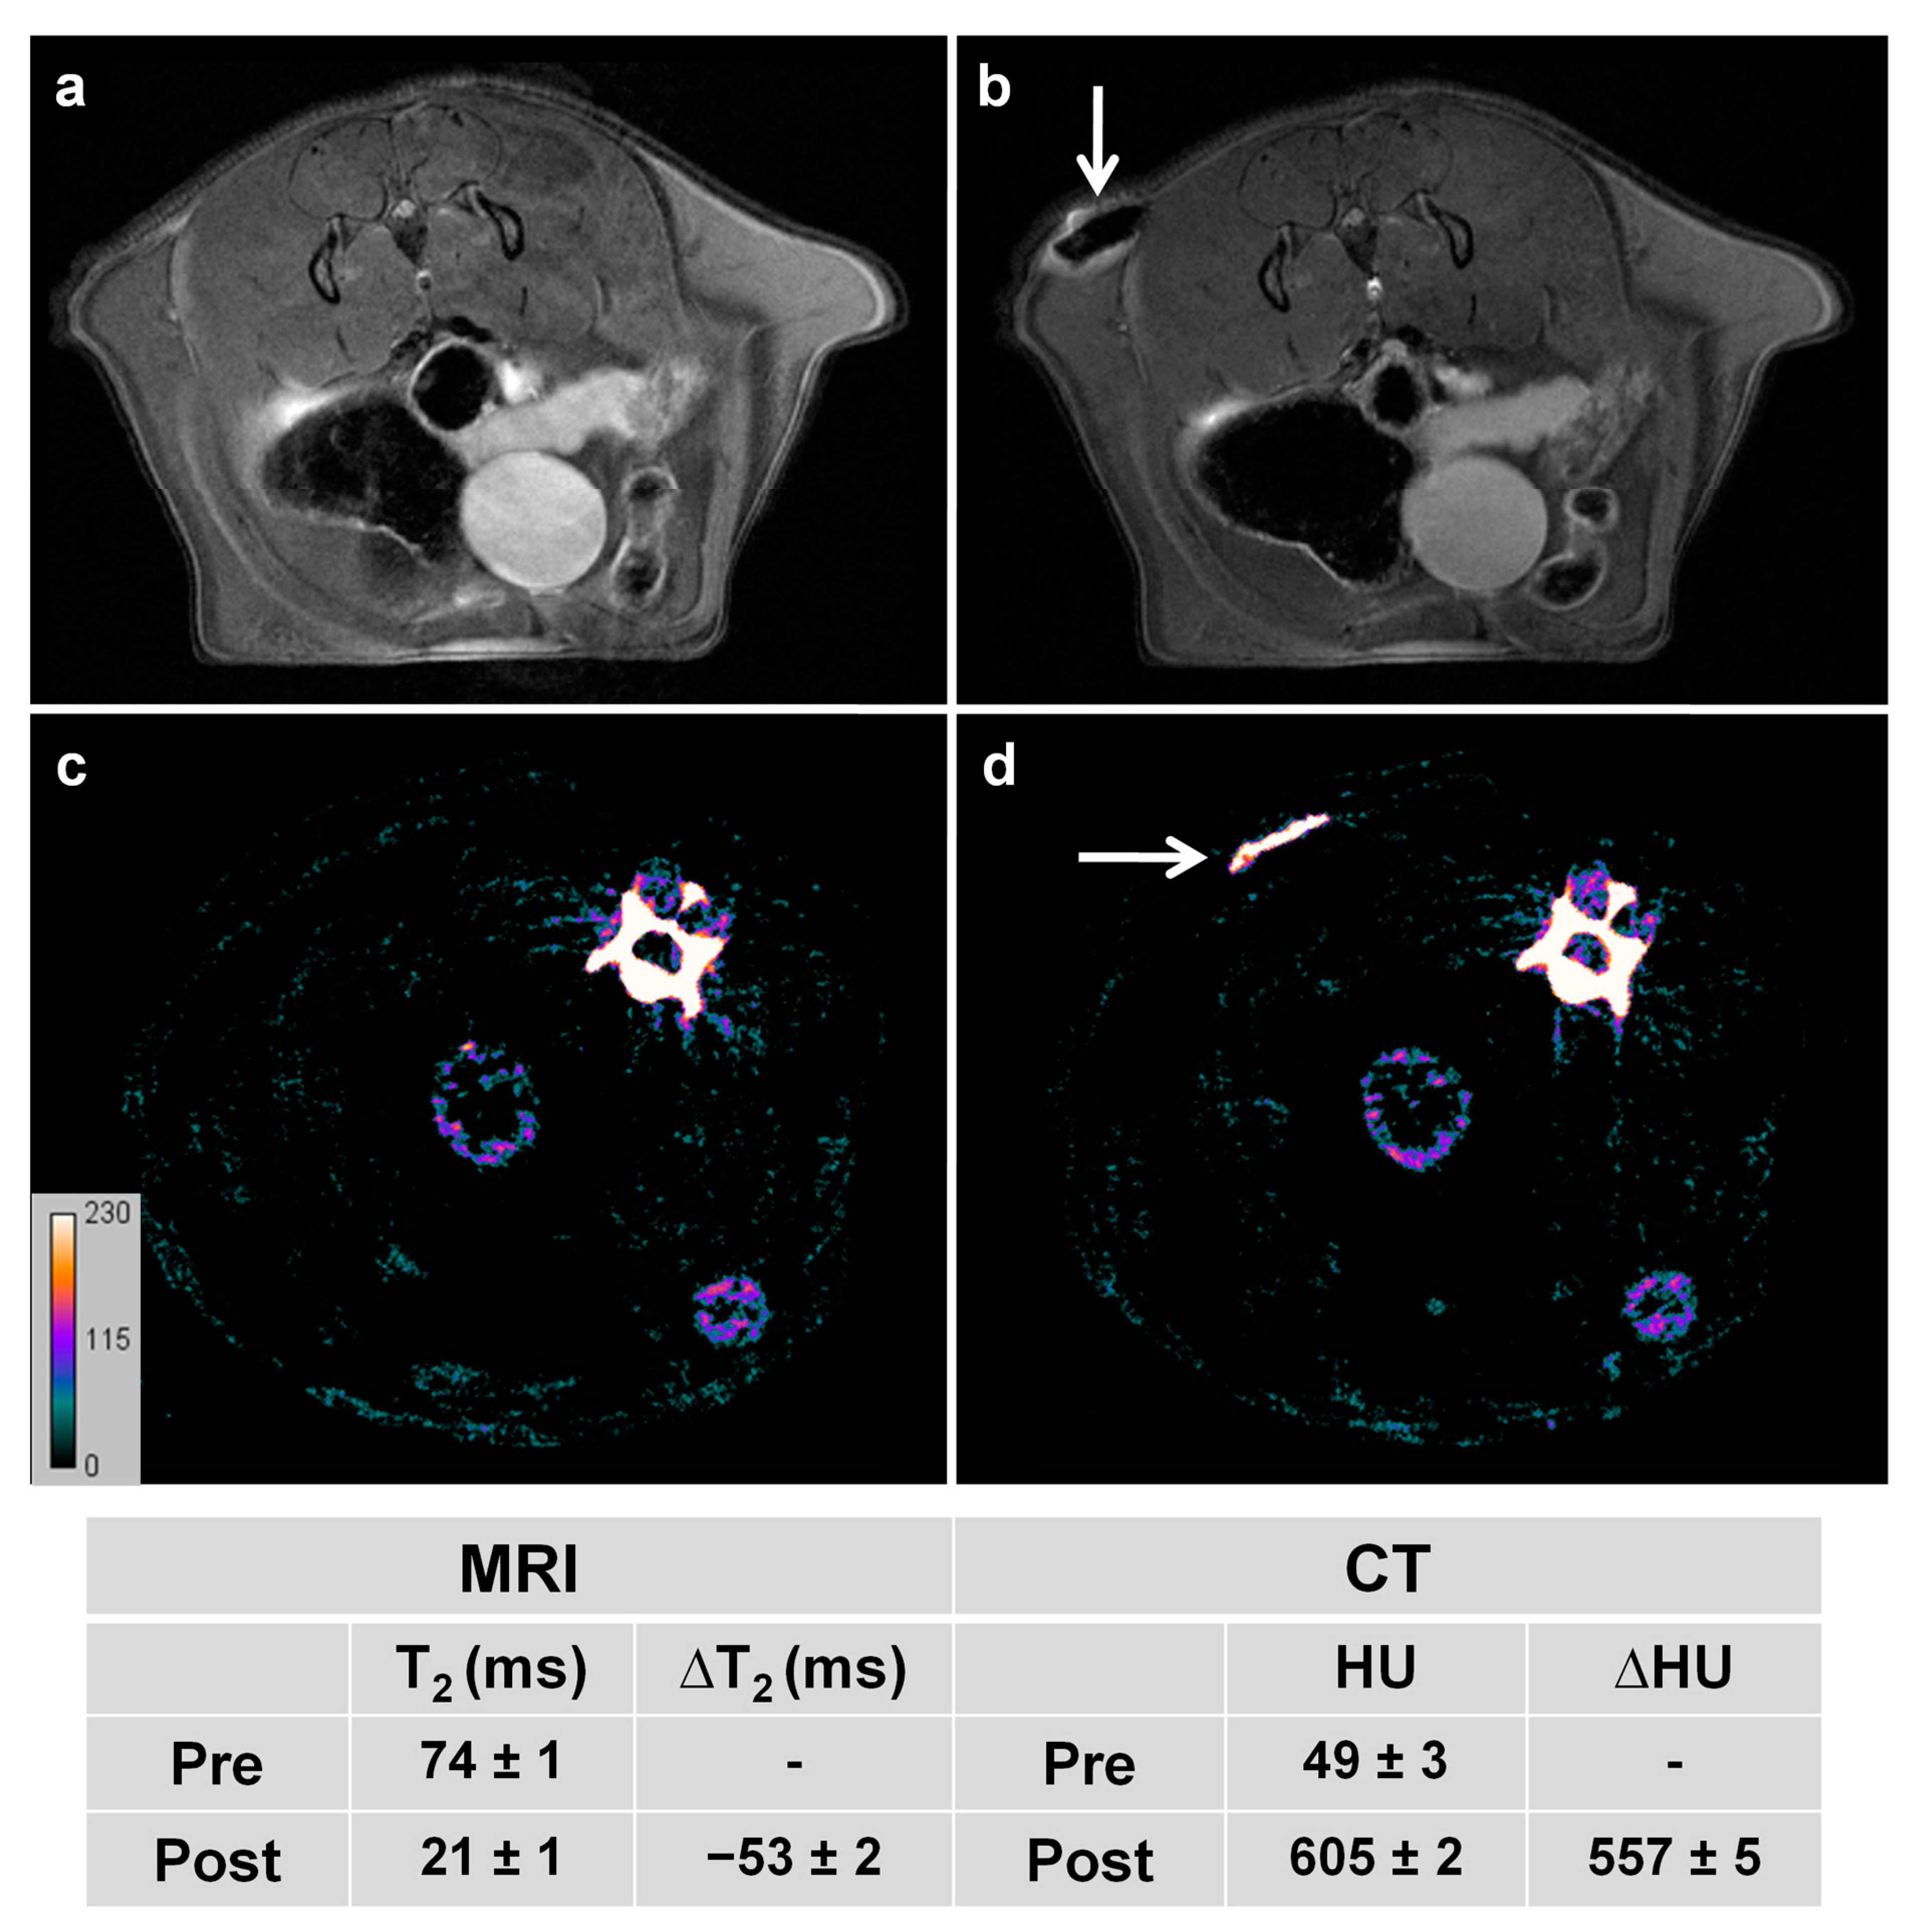

3.6. In Vivo Imaging-Guided TP-Photothermal Therapy